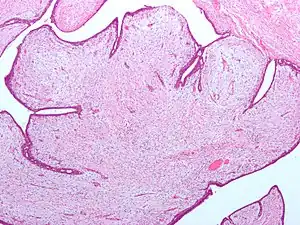

| Fibroepithelial neoplasm (Phyllodes tumor). | |